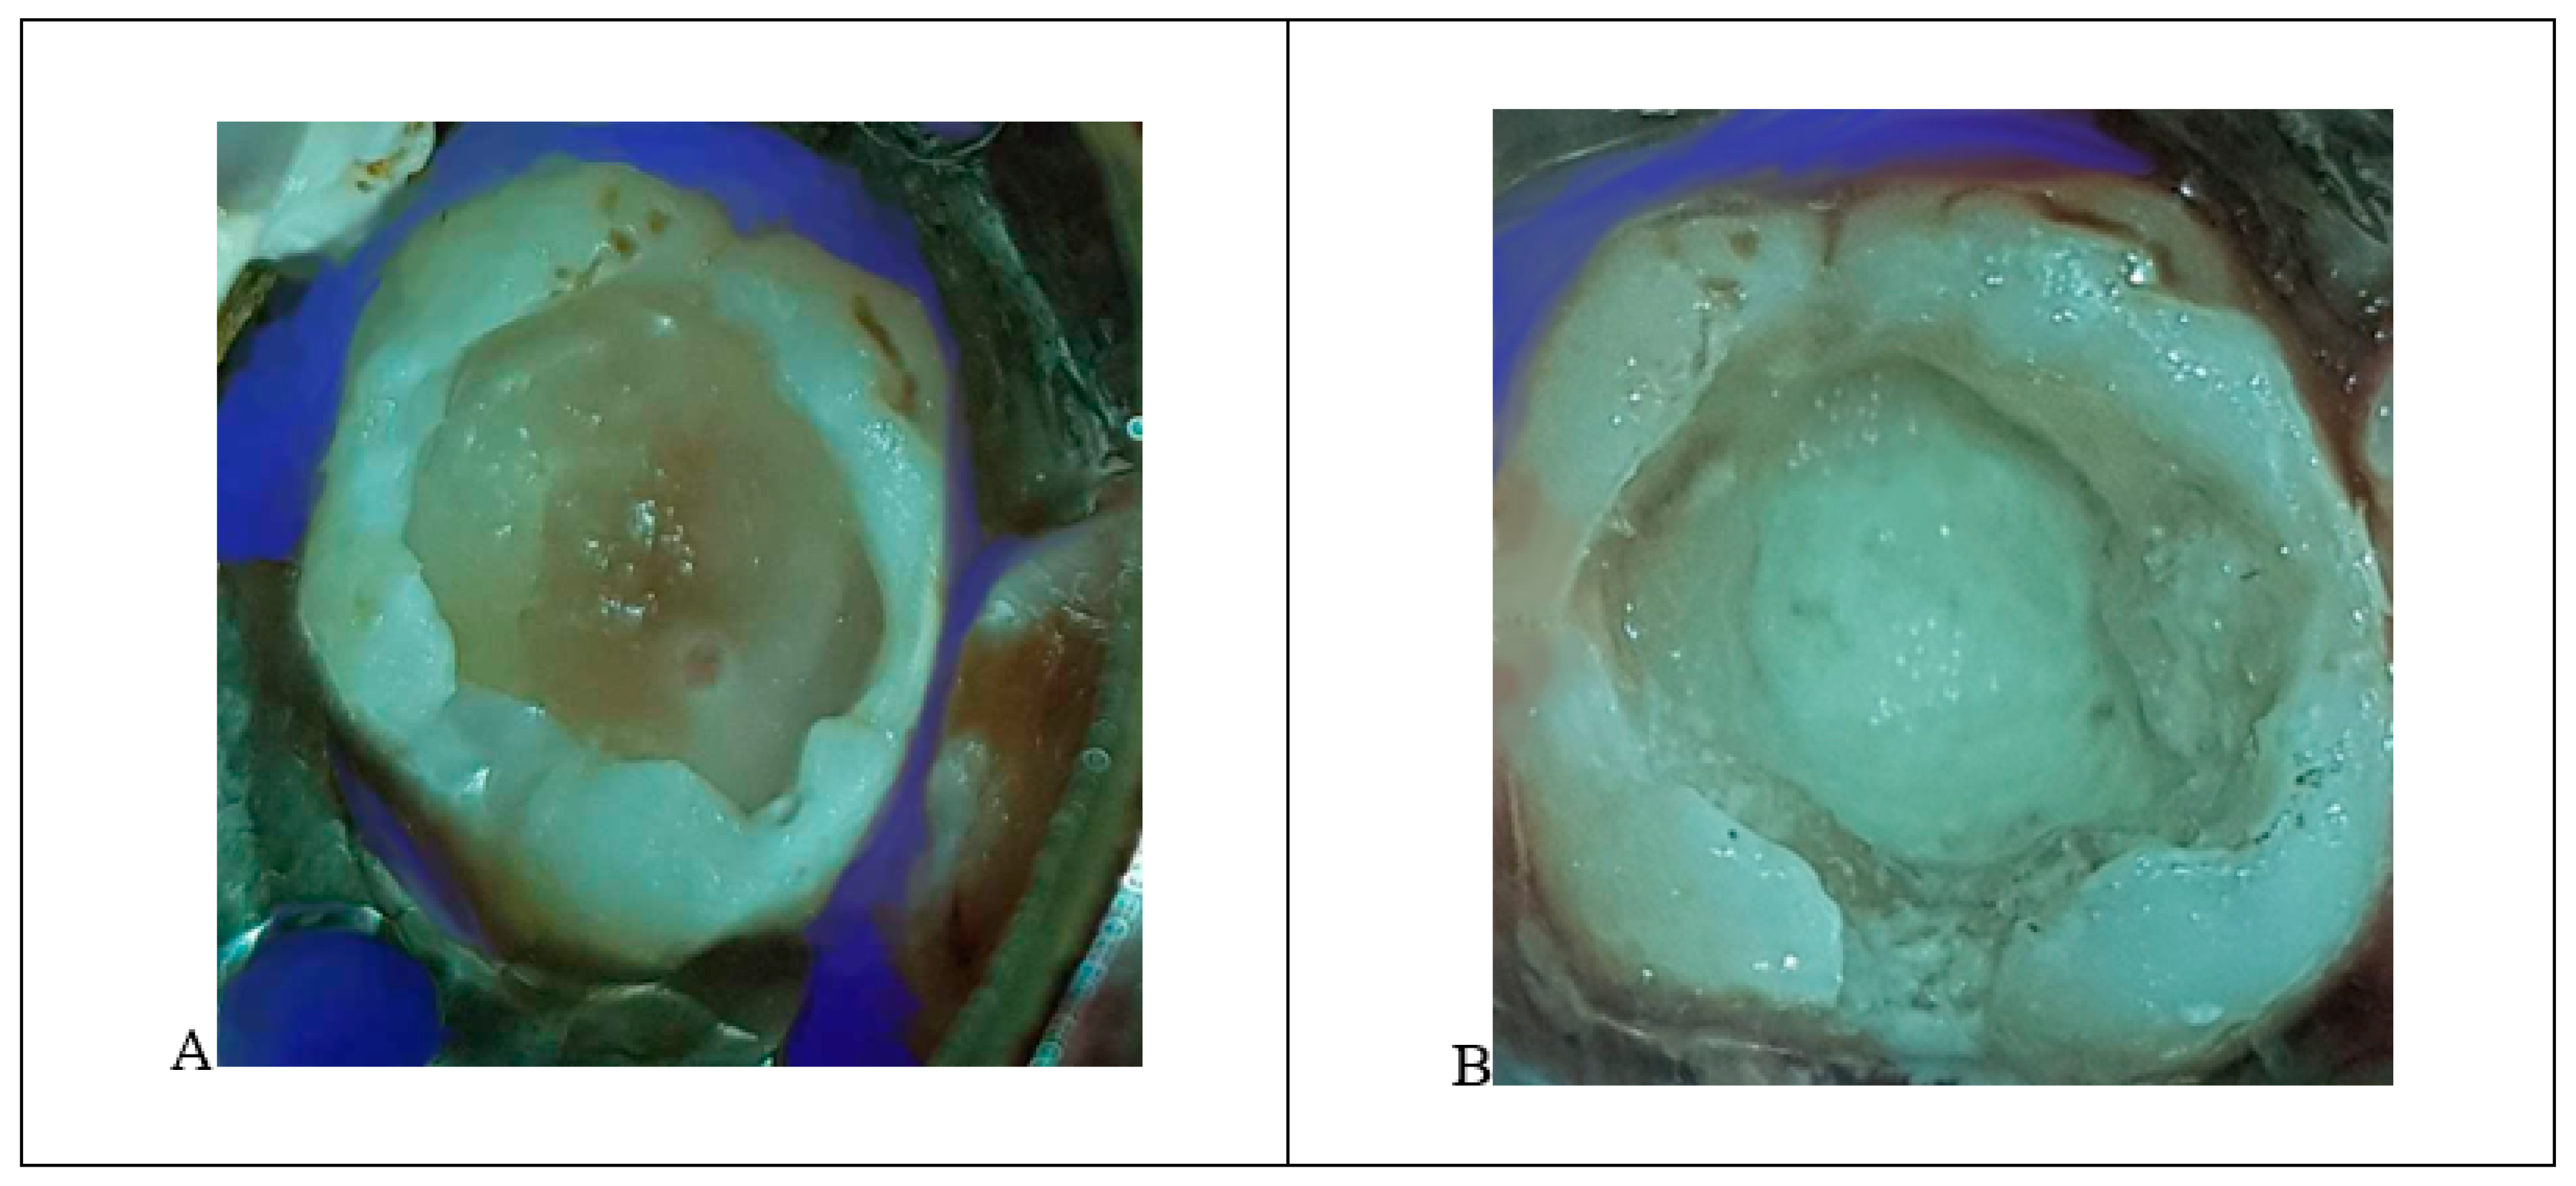

- A pinpoint pulp exposure happened (Figure 6A).

- A coronal pulpotomy was completed by removal of coronal pulp tissue.

- Hemostasis was achieved using 5% sodium hypochlorite and MTA placed as a dressing material over pulp orifices (Figure 6B).

- The tooth was restored like teeth #36 and #46.